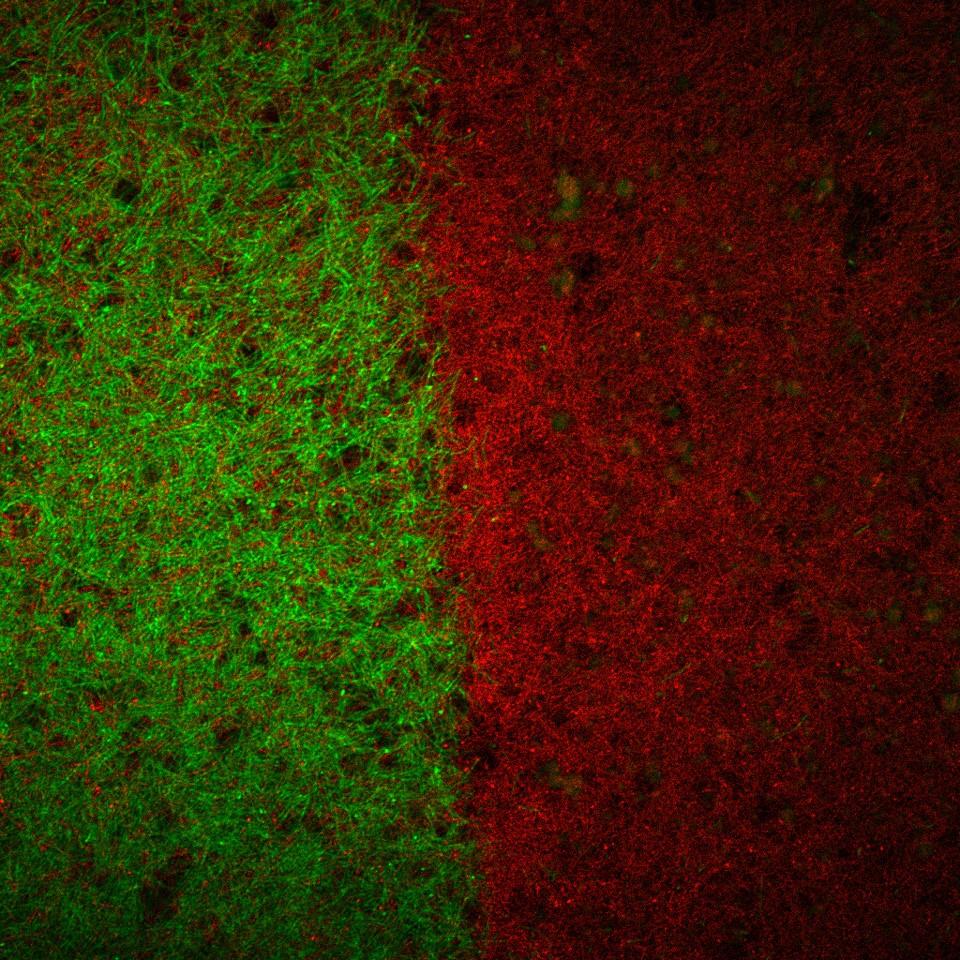

The work, led by Matthew Libera, professor of materials science at Stevens, describes a method for coating implant surfaces with a lattice of microgels: flecks, each 100 times smaller than the diameter of a human hair, capable of absorbing certain antibiotics. The microgels’ behavior is regulated by electrical charges, and the electrical properties of an approaching microbe triggers the microgels to release their antibiotic payload, preventing infections from taking root.

Other self-defensive surfaces currently in development rely on microbes' metabolic byproducts to trigger the release of antibiotics, but the Stevens appraoch doesn't need to wait for metabolism to kick in and can kill even dormant bacterial. The team's microgels are also remarkably resilient, surviving ethanol sterilization and remaining stable for weeks at a time. And, while doing their job killing bacteria and stopping infection, the microgels promote tissue growth around treated surfaces leading to healing.